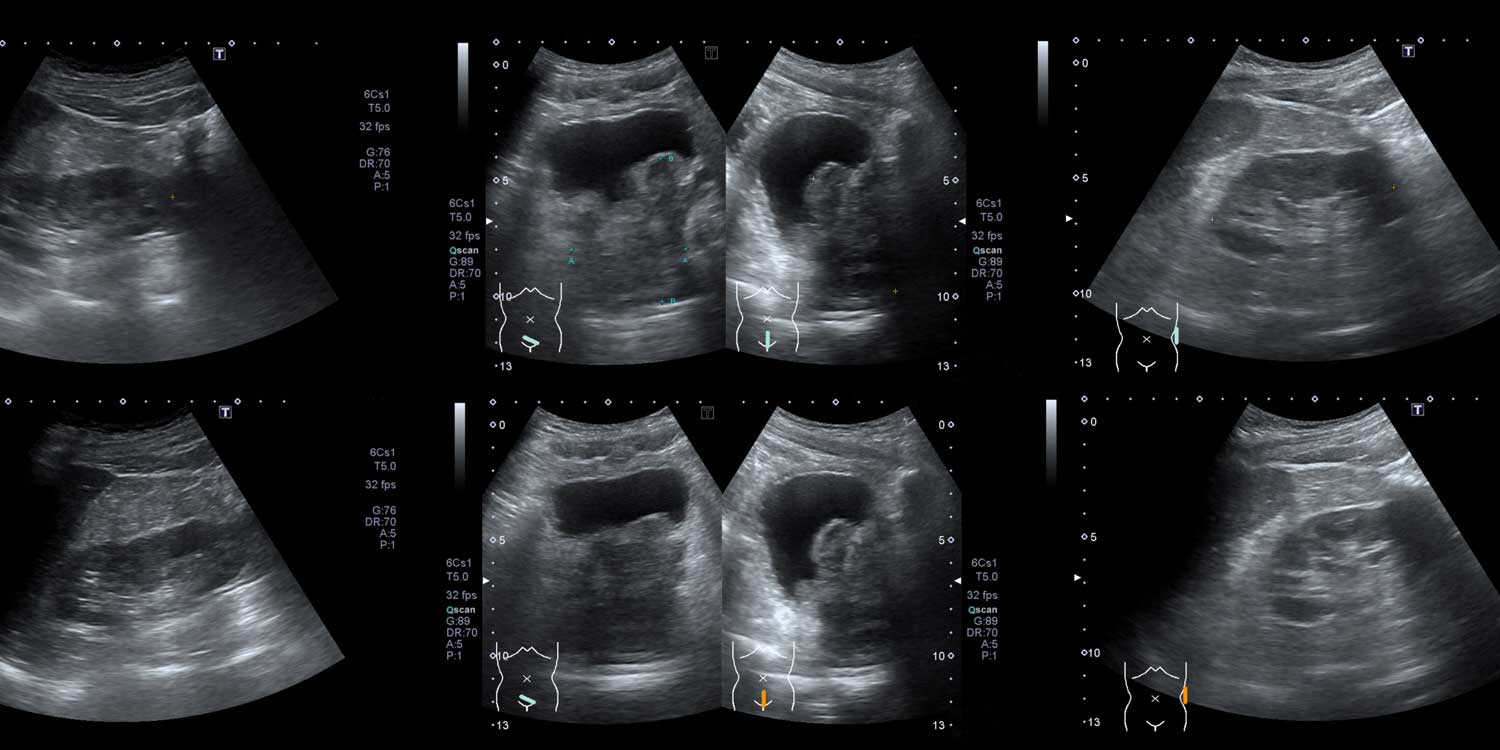

A bladder ultrasound uses sound waves to create real-time images of your bladder — the hollow, muscular organ in your lower pelvis that stores urine. The test can show the bladder’s size, shape, wall thickness, and internal contents. It can also measure post-void residual volume (PVR) — the amount of urine remaining in the bladder after you urinate. A high PVR may indicate incomplete bladder emptying, which can be caused by conditions like enlarged prostate (BPH), neurogenic bladder, or urethral stricture.

Bladder ultrasound may also reveal stones within the bladder, masses or tumors on the bladder wall, trabeculation (thickened wall from chronic obstruction), and diverticula (outpouchings of the bladder wall).

The sonographer applies gel to your lower abdomen and moves a transducer over the area. Images of the full bladder are captured. You’ll then be asked to empty your bladder, after which the sonographer scans again to measure how much urine remains (PVR).